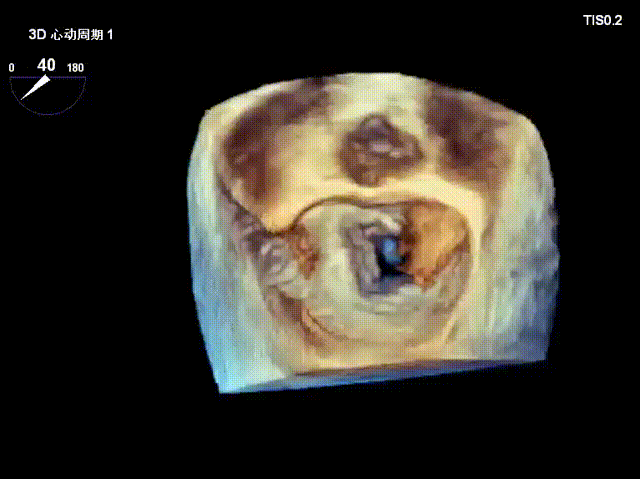

术前经食道超声显示:二尖瓣C1、P1区脱垂,重度关闭不全,彩色多普勒提示大量二尖瓣反流。术前瓣口面积MVA约5cm²,瓣环前后径AP约36.9mm,前叶A1约26mm,后叶P1约15.2mm。

患者全麻后仰卧位,常规消毒铺巾,置入下食道超声探头。于左前胸第五肋间做小切口,暴露心尖,全身肝素化后,心尖穿刺,逐步送入二尖瓣夹系统。术中在超声引导下,分别于C1及A1/P1区植入2枚ValveClamp®二型(MVC-Ⅱf)二尖瓣夹,夹合后超声显示二尖瓣反流明显减轻,随即释放夹子。术后置左侧胸腔引流管1根,逐层关闭胸壁,患者顺利转入ICU观察。

术后即刻反流降为少量,剩余瓣口面积2.57cm²,平均跨瓣压差2mmHg。

术后复查超声心动图显示:二尖瓣轻度返流,三尖瓣中度返流,二尖瓣可见金属夹回声,启闭正常;各心室大小正常,升主动脉不宽,主瓣回声增强,启闭良好;二尖瓣舒张期峰值流速1.4 m/s,功能面积2.1 cm²,跨瓣平均压差约4 mmHg。